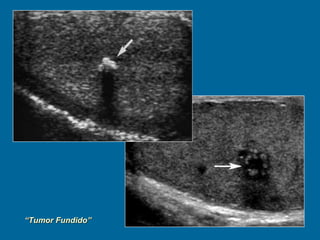

“ Tumor Fundido” fenómeno de "autoquemadura" supone la regresión de un foco de tumor testicular tras la producción de metástasis a distancia, sin conocerse su causa. A pesar de esto, podemos identificar lesiones histológicas características, como son la presencia de una lesión compuesta de tejido colágeno, con células neoplásicas dispersas en su interior. El diagnóstico se realiza mediante el estudio anatomopatológico de la pieza de orquiectomía, debiendo llevarse a cabo ésta en pacientes con tumor germinal extragonadal que presentan alteraciones en la exploración física o en la ecografía.

“ Tumor Fundido”fenómeno de "autoquemadura" supone la regresión de un foco de tumor testicular tras la producción de metástasis a distancia, sin conocerse su causa. A pesar de esto, podemos identificar lesiones histológicas características, como son la presencia de una lesión compuesta de tejido colágeno, con células neoplásicas dispersas en su interior. El diagnóstico se realiza mediante el estudio anatomopatológico de la pieza de orquiectomía, debiendo llevarse a cabo ésta en pacientes con tumor germinal extragonadal que presentan alteraciones en la exploración física o en la ecografía.